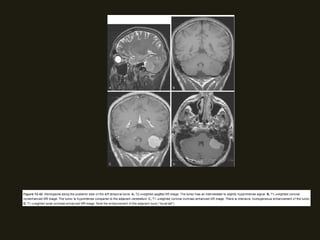

SCHWANOMAS ACÚSTICOS

• Tumores benignos do VIII PC ocorrem no CAI/ângulo

cerebelopontino, surgindo na junção das células da glia com

as de Schwann; Associação com neurofibromatose tipo 2;

• Sintomas dependem da localização do tumor (há compressão

dos nervos coclear e vestibular (CAI) – zumbido, diminuição

acuidade auditiva;

• RM método de escolha (nervo espessado e com realce pelo

contraste; podem ser císticos;); diferencia schwanomas

pequenos dos nervos normais;

NEOPLASIAS BENIGNAS

• Podem ser massas pequenos ou grandes;

• Grandes – distorção da fossa posterior; hérnia de tronco,

hidrocefalia e compressão do IV ventrículo;

• TC alta resolução – mostras alterações ósseas do CAI, porus

acusticus e cápsula óptica; Assimetria dos CAI > 2mm sugere

MASSA!!